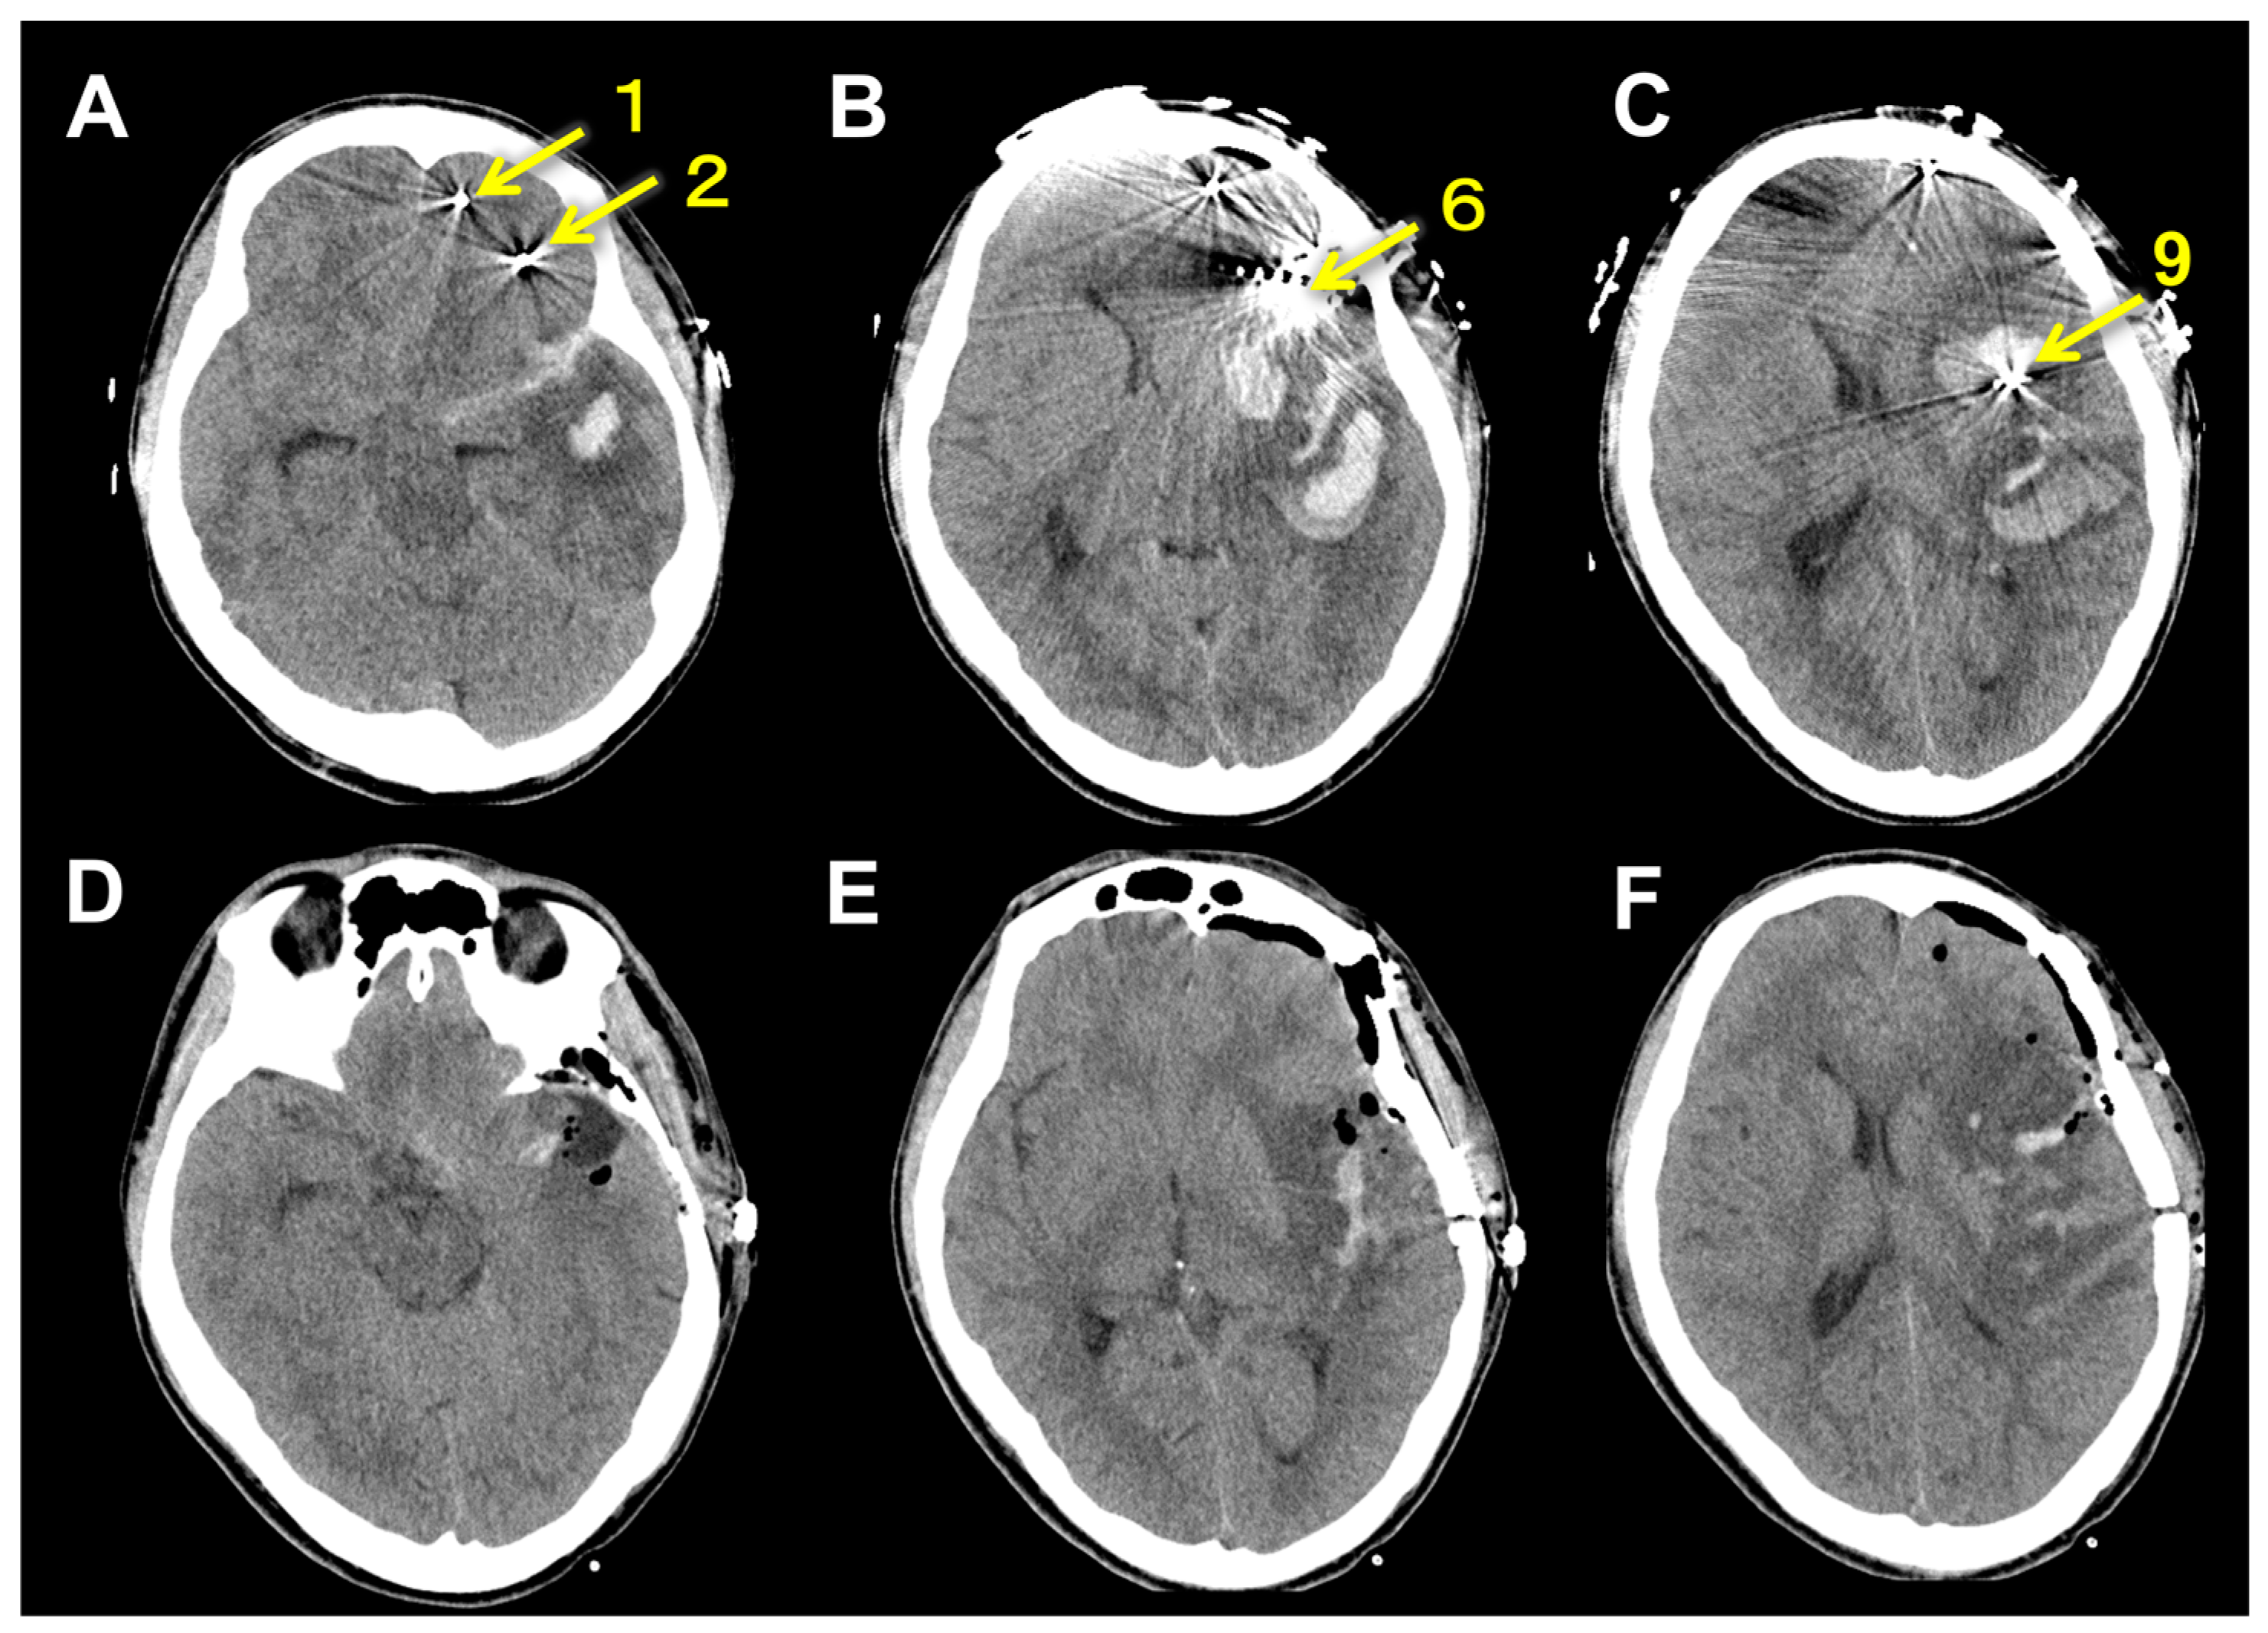

| Electrode # | Side | Entry | Target |

|---|---|---|---|

| 1 | Left | SFG | anterior Orb |

| 2 | Left | IFG | posterior Orb |

| 3 | Left | MFG | anterior Cing |

| 4 | Left | IFG | anterior Cing |

| 5 | Left | FEF | middle Cing |

| 6 | Left | IFG | middle Cing |

| 7 | Left | anterior SFG | SMA |

| 8 | Left | posterior SFG | SMA |

| 9 | Left | PreCG | insula |

| 10 | Right | SFG | SMA |

| 11 | Right | MFG | middle Cing |